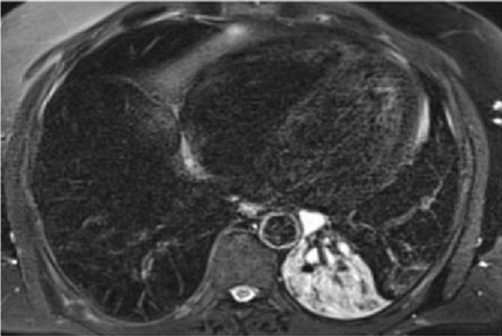

Image radiologique IRM

thoracique en coupe axiale pondérée T2 de cette

tumeur masse paravertébrale prédominantes hétérogène

avec zones en hypersignal et zones de graisseux sur

les images pondérées T2 |